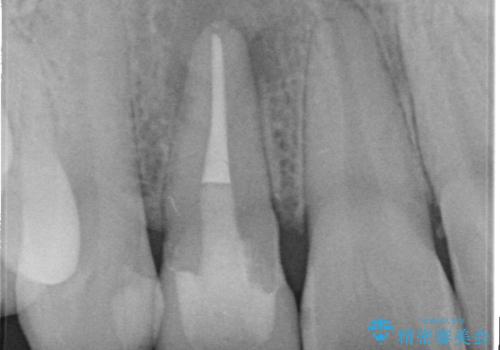

- 前歯が痛いことを主訴に来院されました。

顕微鏡やラバーダムを使用した根管治療を行ってくれる病院を探していたそうです。

根管治療を含め、オールセラミッククラウンにて修復治療を行っております。

当院の根管治療は100%ラバーダムを使い無菌的な処置に配慮して行っております。

今回は歯冠修復にe-maxプレスクラウンを使っています。